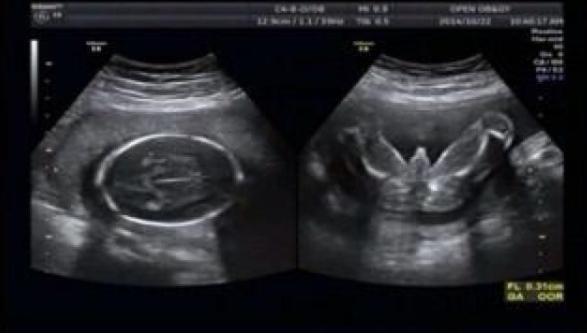

2. 打太极照

这个宝宝可以说是最沉稳的宝宝了,因为他并不活泼好动,而是喜欢和爷爷一样爱好的打太极,因为一直妈妈和公婆的关系都很好,所以在怀孕期间也是一直有公婆悉心照顾。

大概是因为宝宝感觉到他们对妈妈很好了,所以受到感染,这天在做B超的时候,通过医生的镜头可以看到宝宝正在各种打太极,慢慢悠悠的一招一式自己还挺标准,这可让在场的父母都哭笑不得,这也有点太沉稳了吧!